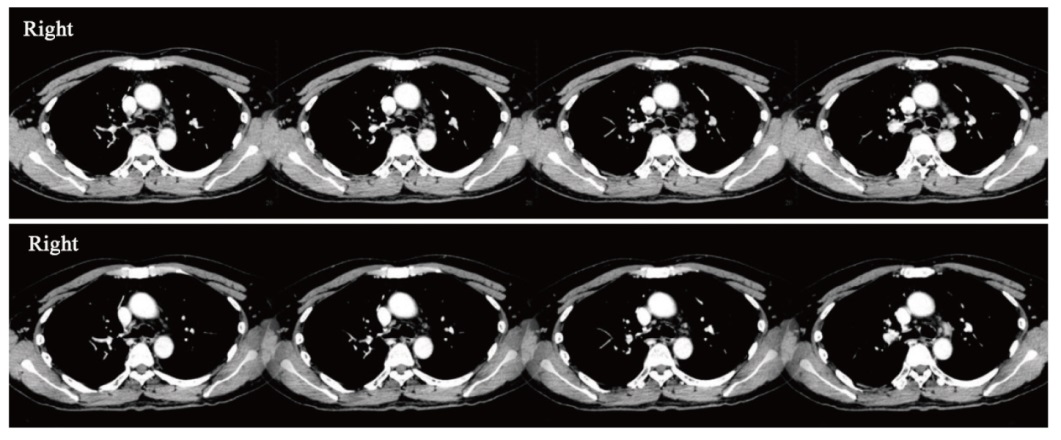

| 图3 第3例患者治疗前后纵隔淋巴结对比 |

| Fig. 3 Comparison of mediastinal lymph nodes before and after treatment in the third patient |